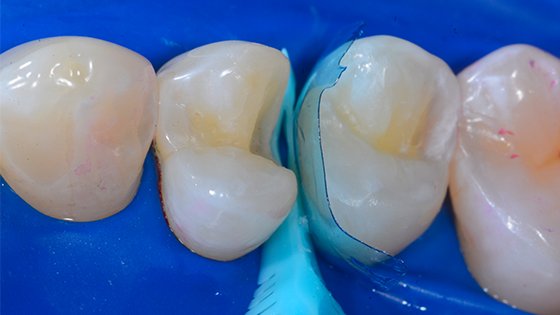

5. As a matrix manager such as in the Spot Weld/push-pull technique with the Bioclear Biofit matrix.

Two dots of Filtek Supreme Ultra Flowable composite are placed after etching and adhesion, but before injection molding. These uncured “spot weld” spots will be light cured momentarily.